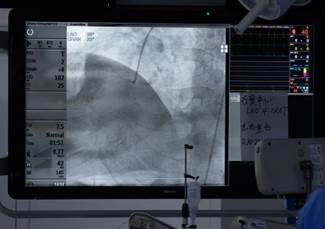

■2021 年 9 月 3 日,医院心内科成功完成东北三省首例一站式、单入路 TAVR + 复杂冠状动脉介入术,填补技术空白。